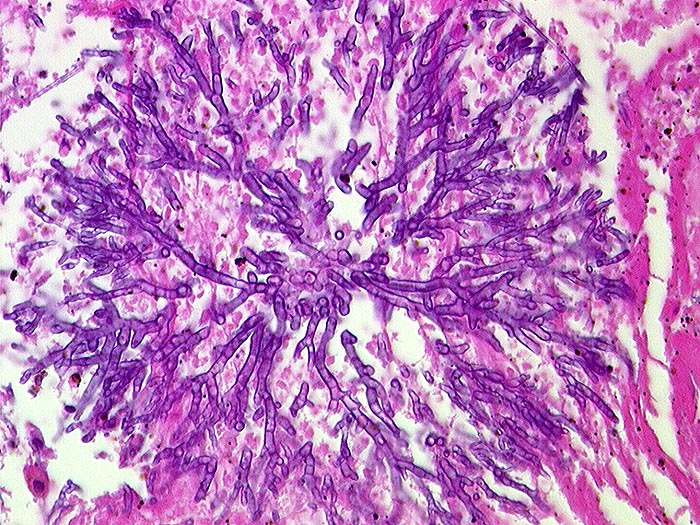

PathoPic – image database / PathoPic ID 547 - Aspergillose

Aspergillose

Entzündung infektiös

Spitzwinklig verzweigte septierte Hyphen.

Histologie